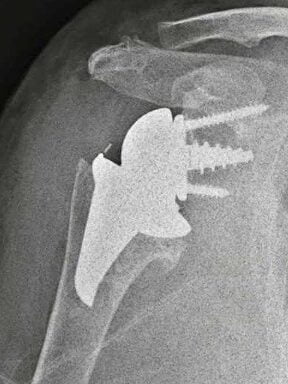

- Αρθροπλαστική: περιλαμβάνει την αντικατάσταση των φθαρμένων οστικών επιφανειών με μεταλλικές προθέσεις. Η αρθροπλαστική ενδείκνυται στις περιπτώσεις που η συντηρητική θεραπεία έχει αποτύχει και συμβάλλει στην ελαχιστοποίηση του πόνου και στην αύξηση του εύρους κίνησης του ώμου. Η επέμβαση πραγματοποιείται με συνδυασμό γενικής και περιοχικής αναισθησίας και απαιτεί συνήθως νοσηλεία μίας ημέρας. Υπάρχουν 2 κύριοι τύποι αρθροπλαστικής ώμου. Η Ανατομική Αρθροπλαστική Ώμου περιλαμβάνει την αντικατάσταση της κεφαλής του βραχιονίου με μεταλλική πρόθεση και την αντικατάσταση της ωμογλήνης με πλαστική πρόθεση. Η ανατομική αρθροπλαστική γίνεται σε νεότερους ασθενείς με ακέραιο στροφικό πέταλο. Η Ανάστροφη Αρθροπλαστική Ώμου πραγματοποιείται σε ασθενείς με σημαντικές ρήξεις στροφικού πετάλου και σε μεγαλύτερους σε ηλικία ασθενείς. Στην ανάστροφη αρθροπλαστική, η κεφαλή και η κοίλη επιφάνεια («κούπα») τοποθετούνται αντίστροφα από το φυσιολογικό (κοίλη επιφάνεια στην κεφαλή του βραχιονίου και γληνόσφαιρα στην ωμογλήνη). Η επέμβαση είναι πολύ επιτυχημένη και έχει γίνει εξαιρετικά δημοφιλής παγκοσμίως τα τελευταία χρόνια, με τα αποτελέσματα να είναι πολύ ενθαρρυντικά.